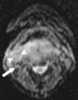

Necrotic lymph node metastasis